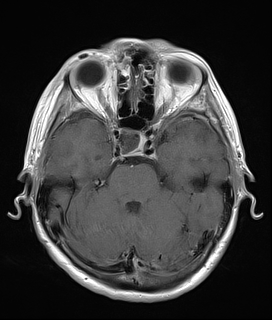

W badaniu tomografii komputerowej (TK) głowy oraz angio-TK stwierdzono krwawiącą malformację tętniczo-żylną (AVM) zlokalizowaną w lewej półkuli móżdżku.

W przypadku prezentowanej pacjentki nie stwierdzono objawów neurologicznych poza bólem głowy. Po wstępnej diagnostyce została przekazana do Oddziału Neurochirurgicznego Szpitala Kopernika w Łodzi. W trybie pilnym wykonano angiografię cyfrową (DSA), która precyzyjnie uwidoczniła AVM.

Przeprowadzono embolizację części tętnic zaopatrujących AVM, co zmniejszyło ryzyko krwawienia śródoperacyjnego. Następnie wykonano kraniotomię podpotyliczną lewostronną z całkowitym usunięciem malformacji. Zabieg przebiegł bez powikłań, po zabiegu u pacjentki nie stwierdzono deficytów neurologicznych. Kontrolna angiografia potwierdziła całkowite usunięcie zmiany, co pozwala uznać pacjentkę za wyleczoną.